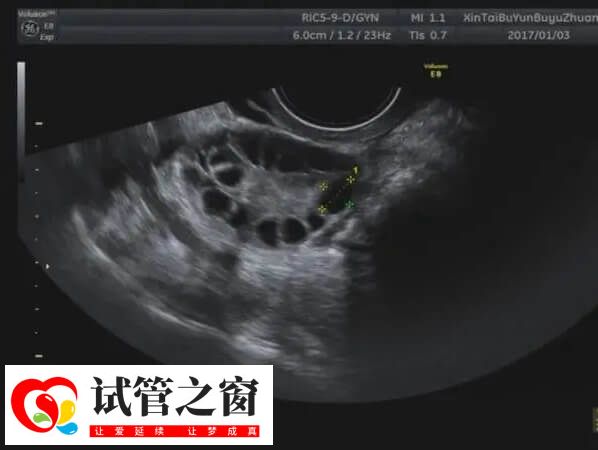

多囊卵巢綜合癥是一個以女性月經(jīng)不調(diào)、不孕為常見臨床表現(xiàn)的病,是生育年齡女性常見的一種內(nèi)分泌代謝紊亂疾病,對于這類患者在促排期間還發(fā)現(xiàn)血糖和胰島素高的情況下,可通過以下方法改善。